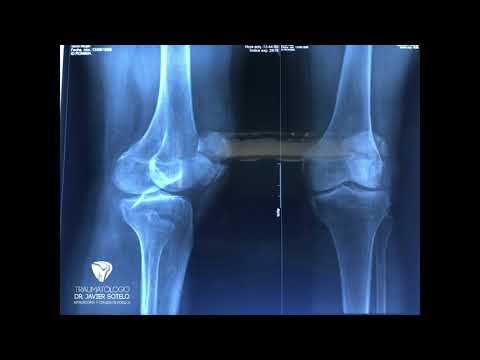

La traumatología es la especialidad médica que se enfoca en el diagnóstico y tratamiento de lesiones y condiciones que afectan el sistema musculoesquelético. Gracias a los canales de traumatología en plataformas digitales, pacientes y profesionales pueden acceder a información valiosa sobre lesiones, rehabilitación y prevención de problemas ortopédicos. Estos canales son recursos esenciales para aquellos que buscan mejorar su salud física y conocer más sobre el cuidado de su cuerpo.